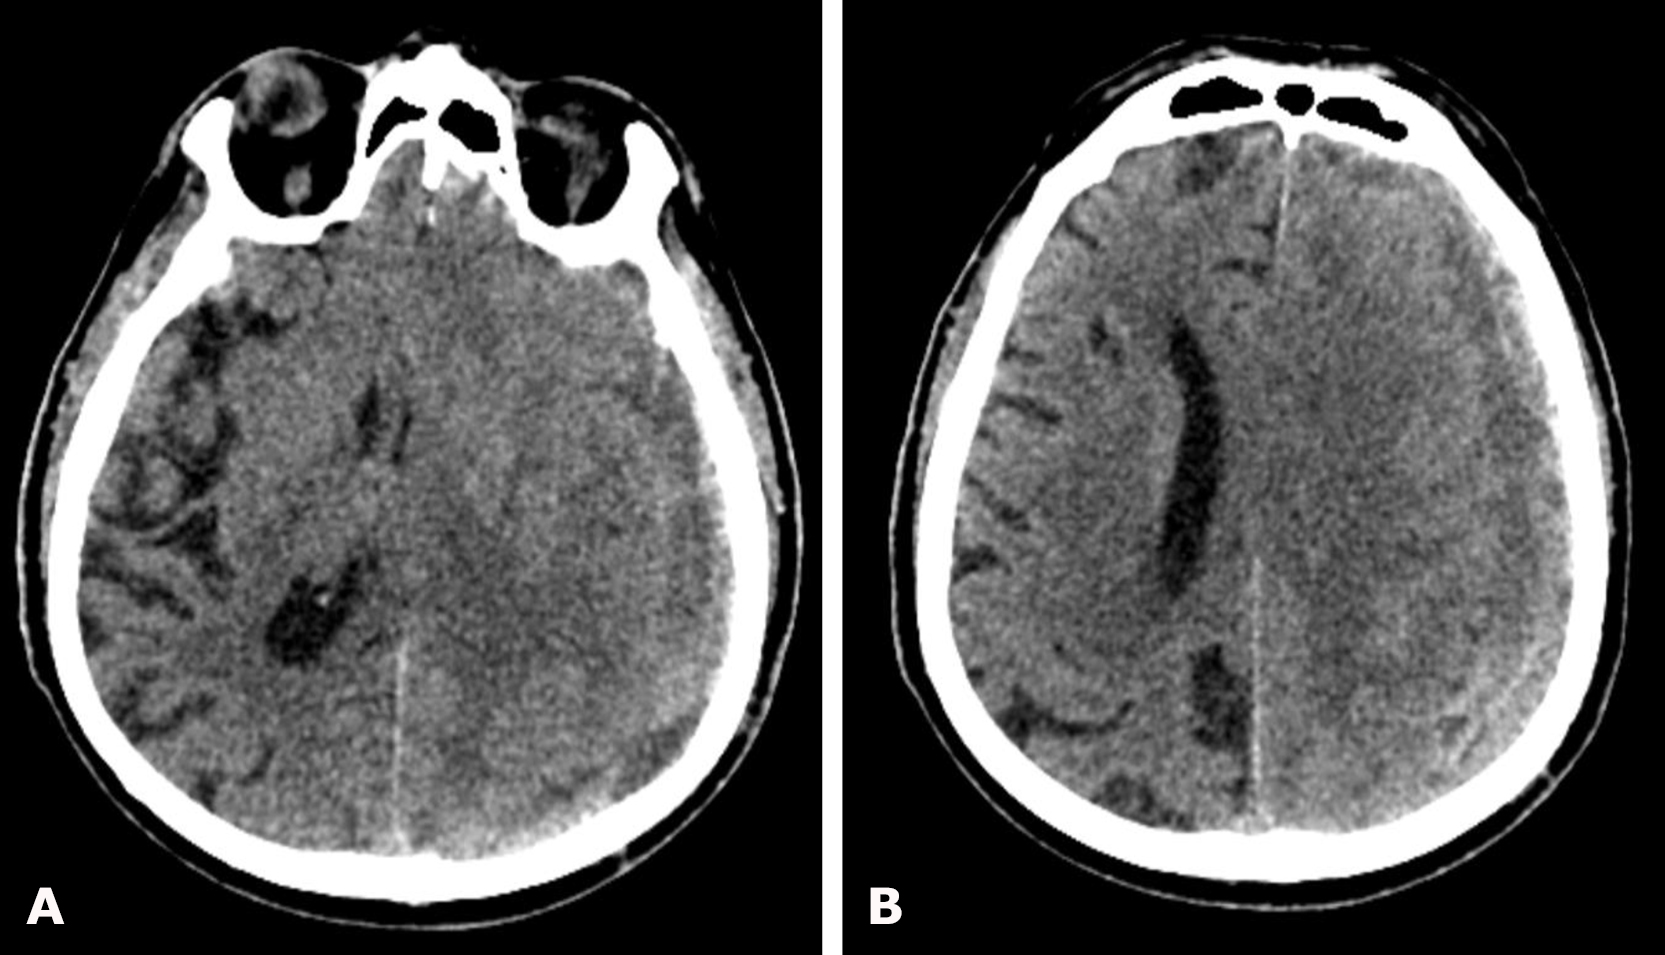

Non-contrast brain CT demonstrated a left-sided hemispheric multiloculated cSDH with dimensions (thickness/length/height) of 17/145/104 mm and an 8-mm midline shift to the right (Fig. 13).

Fig. 13. Preoperative brain CT: A, B – axial projections demonstrating a left-sided hemispheric multiloculated cSDH with marked compression and edema of the left cerebral hemisphere

Given the CT findings and the severity of the patient’s condition, emergency surgery was performed for life-saving indications: osteoplastic craniotomy in the left parietal region, evacuation of the left-sided multiloculated cSDH, and inflow–outflow drainage of the left subdural space on June 11, 2024 (Fig. 14).

Fig. 14. Control brain CT on postoperative day 1: A, B – axial projections. The yellow arrow indicates radiopaque drains of the inflow–outflow drainage system